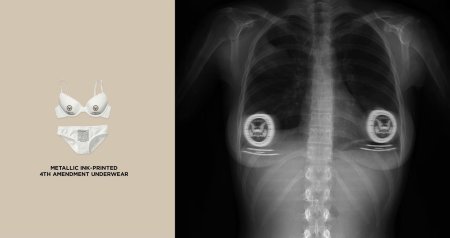

Скелет в лифчике